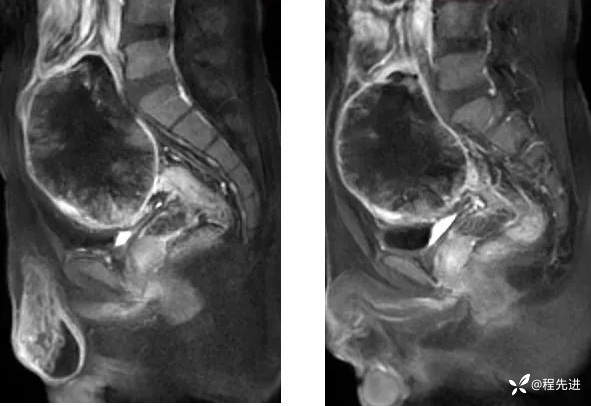

【腹盆】特别精彩病例|下腹痛20余天,男性病人腹腔巨大肿块该如何诊断

【患者信息】:男,41岁

【主诉】:下腹痛20余天

既往史:隐睾

肿瘤标志物:甲胎蛋白(AFP)>10000

增强: